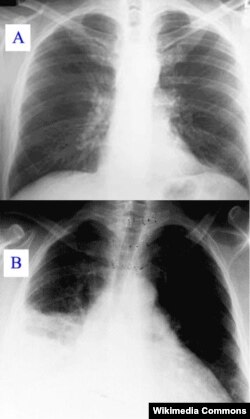

X-ray showing clear (A) and pneumonia infected lungs (B)

Once it gets in a person's lungs, the alveoli, or air sacs that take in oxygen, swell and fill up with fluid. This makes breathing difficult and painful, and can also limit the amount of oxygen a person takes into their body with each breath. It also causes fever, chills and coughing.

Because the symptoms mimic those of the flu and the common cold, diagnosis sometimes takes a visit to a doctor, who will listen to your lungs for "crackling, bubbling, and rumbling sounds when you inhale," according to the American Lung Association (ALA). A follow up chest X-ray may also be necessary.